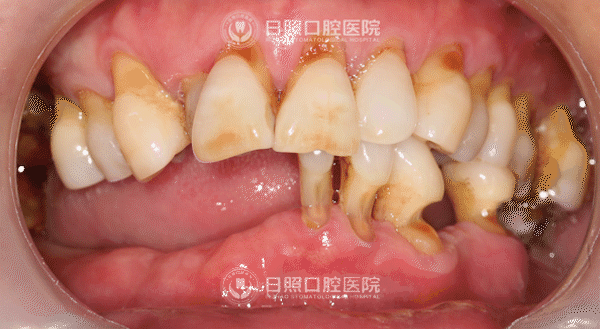

家住日照市区的老刘今年60岁,已经有10余颗牙齿陆续脱落,数月前,老刘下颌仅剩的5颗牙齿也出现松动,严重影响了正常咀嚼,让他饱受困扰。近日,日照口腔医院颌面外二科主任、种植专家王新全,为他成功实施了“下颌半口即刻种植即刻修复”手术,实现了“当天种牙当天用”,帮助老刘重享“吃嘛嘛香”的生活。

术前,刘大叔下颌仅剩5颗牙齿